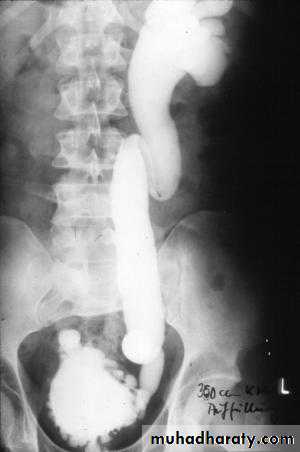

Mega ureter

IVU demonstrate elongated stretch LT PCS due to multiple left sided renal cysts(spider leg sign)

Absent RT K Ectopic LT kidney

LT SIDED VUR ( HN&HN ) NEUROGENIC BLADDER Christmas tree sign